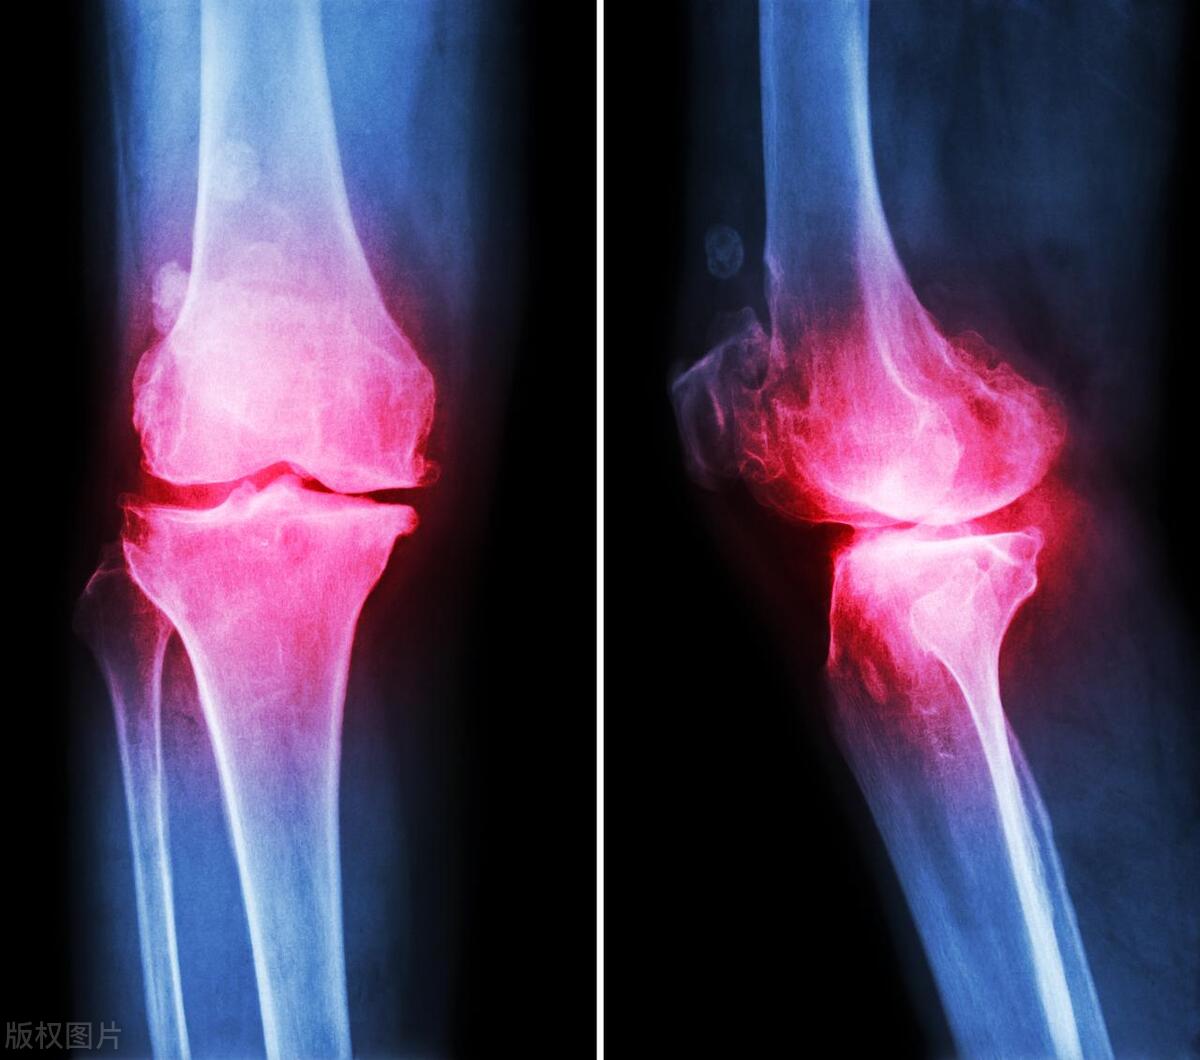

(4)骨折部位 X 线片或 CT 扫描及三维重建检查见骨折线即可明确诊断,并能确定骨折 分类及其移位情况。疑伴有韧带损伤者,可酌情选用 MRI 检查。

二、 影像学检查:下肢深静脉血栓主要诊断征象:

①对血管内的状况进行检查时利用的是声波反射,当低回声、等回声、强回声等异常反

射出现时就表明血栓在血管内出现了;

②生成血栓的管腔不被压瘪;

③如果血栓完全堵塞病人的深静脉,血流流动的信号就不会出现在病变位置或其远、近 两侧,血流也不会随着远端肢体的挤压而升高

④如果血栓只是堵塞了管腔的局部,充盈缺损的现象就会出现在管腔内,期相性也随之 消失。

三、静脉造影:能够将血栓的形态、大小、位置进行精准的发现,被称为“金标准”。